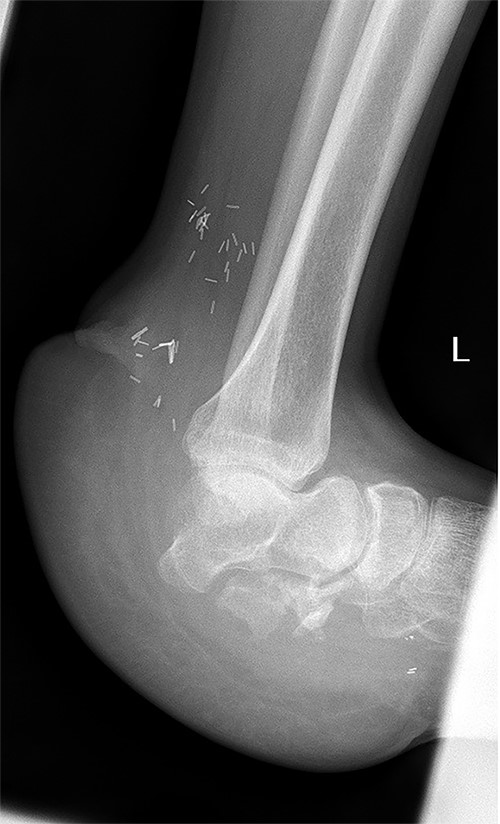

A 32-year-old male, without any known medical illnesses, presented after sustaining a blast injury to the left foot by a landmine. Upon presentation the patient was hemodynamically stable, with isolated large left hindfoot defect associated with exposed vital structures (talonavicular joint, tibial nerve and posterior tibial artery and vein), both tibial nerve and posterior tibial artery and vein where intact with intact sensation over the remaining skin of the foot; (Fig. 1). X-ray showed total calcaneus bone loss (Fig. 2), computed tomography angiogram showed intact anterior and posterior tibial arteries, fractured talus and complete loss of calcaneus bone.

X-ray of the left foot showing complete loss of the calcaneus bone.